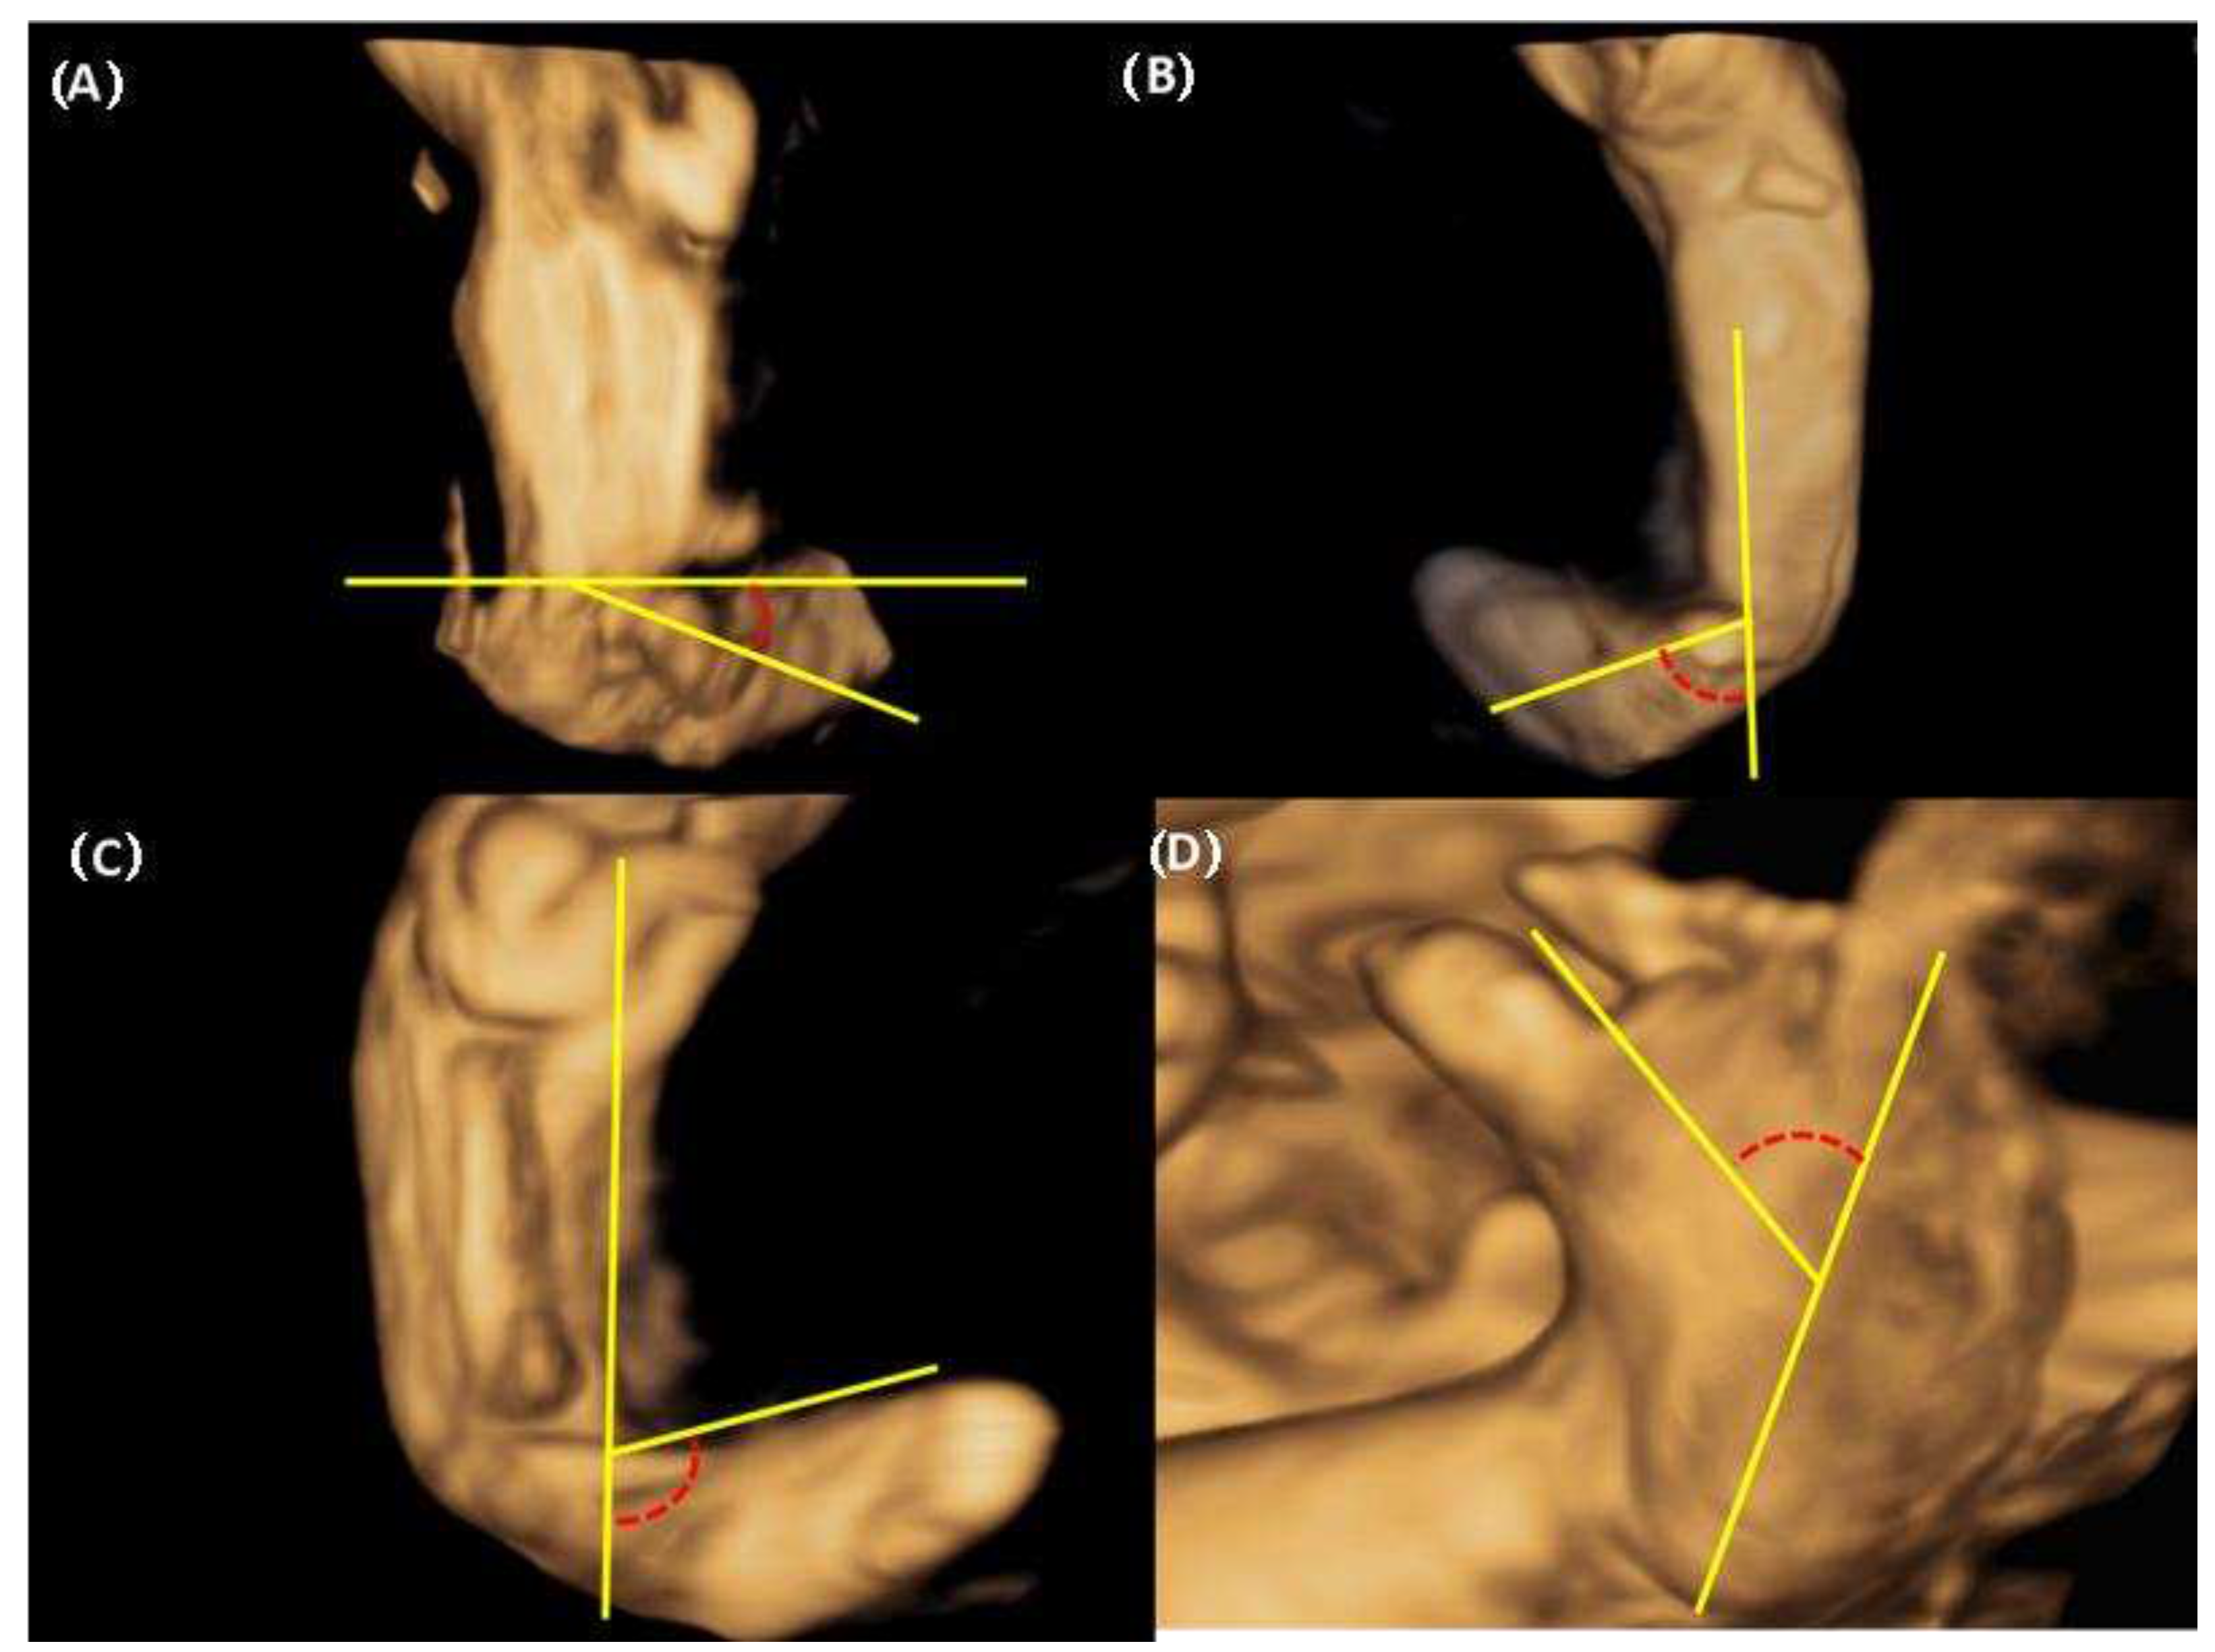

We were able to freely handle the 3D captured image at 360 degrees and reproduce the desired planes, reconstructed the sagittal, coronal (anterior and posterior), and horizontal planes. Below is an explanation of the deviation value measured at each plane (Figure 2). 1. Equinus deviation: the fixation of the foot in a plantar inward position in the sagittal plane. we measured the deviated angle between the line perpendicular to the tibia and the midline of the dorsum. 2. Varus deviation: the medial deviation of the foot in the posterior coronal plane. we measured the angle between the line parallel to the tibia and the midline of the calcaneus 3. Calcaneopedal block deviation: derotation of the calcaneal forefoot block in the frontal coronal plane. we measured the angle between the medial line of the calf and the inner line of the talus.4. Forefoot adduction in the horizontal plane. we measured the angle between the midline of the plantar and the inner line of the big toe. Calf volume and circumference were also measured because calf muscle dystrophy is a significant clinical feature of congenital clubfoot and is one of the scoring factors in the Demeglio method. First, we created a plane in which the tibia and fibula are observed. Second, designating the end of the ossified tibia bone, we divided it horizontally into five sections and measured the circumference using calipers on the skin surface. The largest calf circumference and automatic calculated calf volume were recorded (Figure 3).

Figure 2. The three dimensional assessment of deviation between foot and calf and plantar deviation of foot (A) Equinus deviation in the sagittal plane (B) Varus deviation in the frontal plane (C) Derotation around the talus calcaneo-forefoot in the coronal plane (D) Adduction forefoot on forefoot in the horizontal plane.